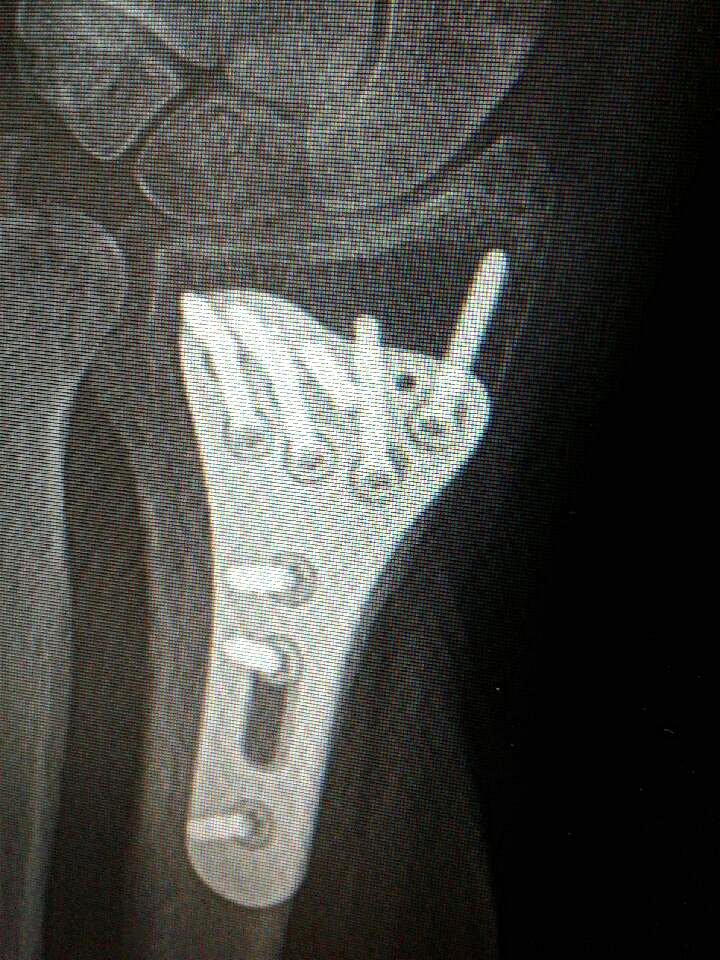

Look on the right side of my wrist to see the plate, shaped like an ice scraper. (Minnesota Prairie Roots copyrighted file photo 2018)

Bear with me. I also have an implant in my left wrist, the result of a 2018 fall which shattered my wrist. Ten screws hold that wrist plate in place. When the weather changes, I notice discomfort in my wrist. Likewise in my right shoulder. I broke that in 2017 after missing the last step on a hospital stairway while on my way to donate blood.

This is a photo snapped with a cellphone of the implant in my wrist, held in place by 10 screws. (Minnesota Prairie Roots copyrighted file photo 2018)